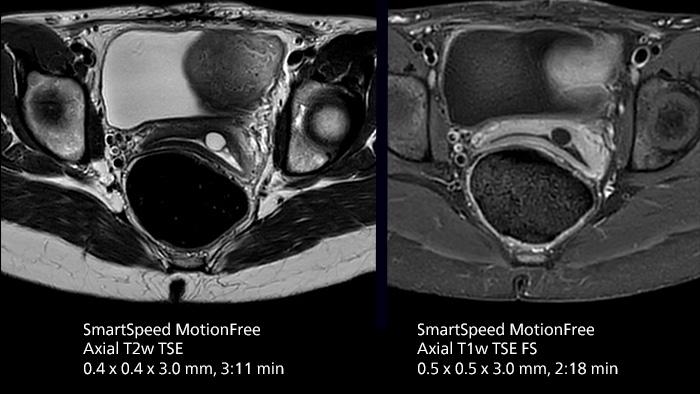

After using Philips SENSE, Mermaid Beach had adopted Compressed SENSE that offers a k-space sampling approach to speed scans while preserving details. “And now SmartSpeed enables denoising the sparse under-sampling in a new way that has allowed us to increase acceleration and bring image quality to a whole new level,” notes Kennedy, “It’s truly revolutionized our MRI work space, especially for difficult patients.”

Philips SmartSpeed has multiple approaches to denoising. Raw k-space data, coil sensitivity and coarse background information are all used and reconstructed with artificial intelligence (AI) to provide true resolution in shorter scan times1 with more sequences. Kennedy states, “I noticed that since the introduction of SmartSpeed, our day is a lot less stressed. When complicated exams need extra time, we just get on with them. And if we need to do something new or extra, we have the time for it and our workflow is still a lot more efficient.”

The broad applicability of SmartSpeed allowed the imaging center to use this technology across many scan types, including non-cartesian imaging as used for motion correction in uncooperative patients or challenging anatomies.

“We use SmartSpeed frequently on difficult areas such as the abdomen and chest where it is common to see respiratory motion and other bowel motion,” says Kennedy. In MSK scans they use SmartSpeed not only for speeding up their exams, but also to reduce slice thickness and improve resolution “We may be increasing the number of slices, but we’re still doing this in less time than we were previously.”